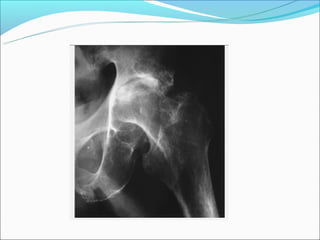

AR – Migração axial da cabeça do

fêmur